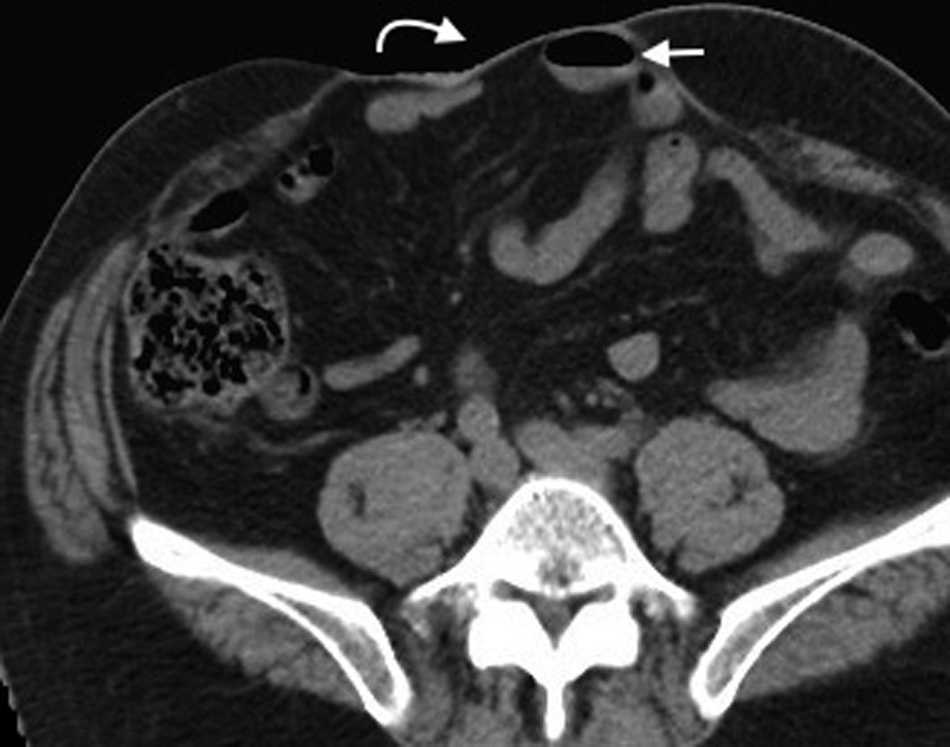

Eventraci??n

Representa una protrusi??n subcut??nea del contenido intraabdominal a trav??s de una zona debilitada de la pared abdominal o lumbar como consecuencia de una intervenci??n quir??rgica, una brecha posterior a un traumatismo cerrado o una malformaci??n cong??nita. Puede producirse en cualquier incisi??n quir??rgica sobre la pared abdominal, incluyendo los orificios de los trocares de laparoscopia. Es m??s frecuente en las incisiones verticales que en las transversales1.

La mayor??a se desarrolla durante los primeros 4 meses despu??s de la cirug??a, un per??odo cr??tico para la curaci??n de las capas musculares de la pared abdominal18. Se puede manifestar con signos y s??ntomas en su primer a??o, aunque un 5-10% permanece silente durante un per??odo prolongado hasta su detecci??n2.

Los estudios radiol??gicos pueden ser utilizados para visualizar los segmentos herniados y evaluar las complicaciones asociadas, tal como la obstrucci??n intestinal. Muchas veces se usan en evaluaciones dificultosas, como en pacientes de marcada obesidad o que tienen contenido herniario f??cilmente reductible o cicatrices de gran tama??o19 (figs. 12 y 13).